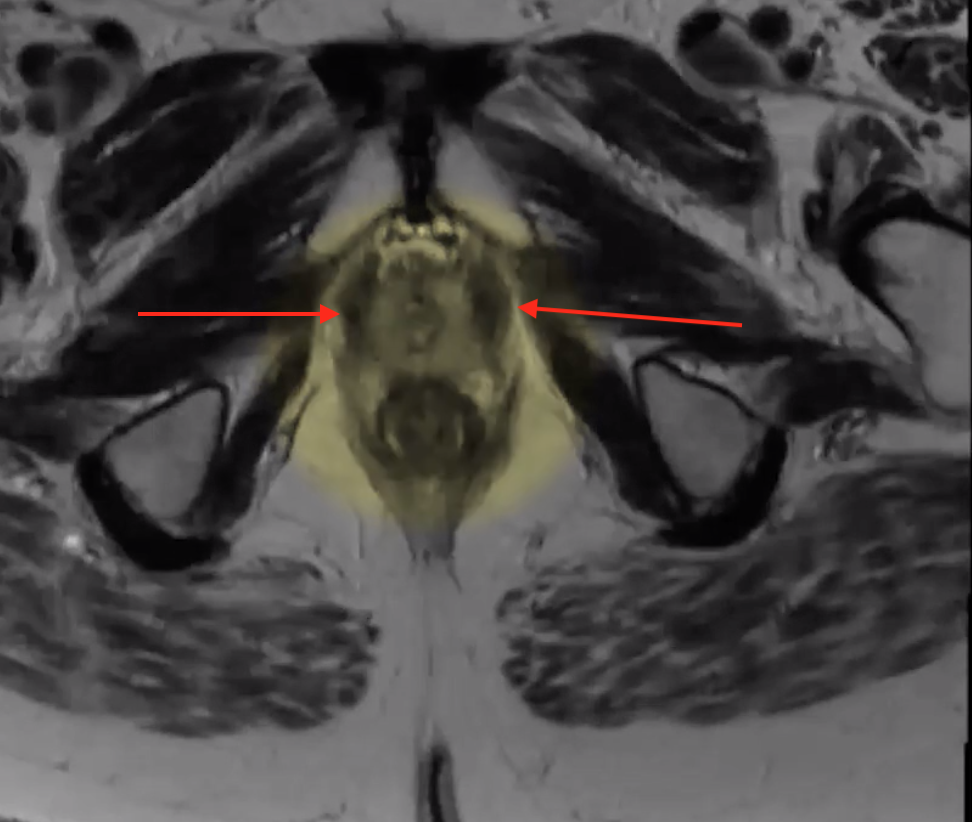

Puborectalis

• U shaped muscle on either side

• Will get an oblique-axial view which is used to look down the lumen of the rectum

• Will get an oblique coronal view which is used to look down the lumen of the distal rectum and anus